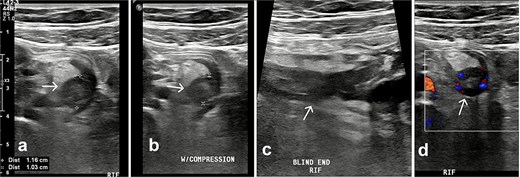

Pelvic ultrasound demonstrated a non-compressible, blind-ended tubular structure in the right iliac fossa measuring 11 mm with increased wall vascularity, suggestive of acute appendicitis (Fig. 1).

Ultrasound of the right iliac fossa. Transversal ultrasound image of the appendix (white arrow). (a) Before compression. (b) During compression, showing an uncompressible distended appendix (cursors). (c) At the level of the right iliac fossa, there is a blind-ending tubular structure.